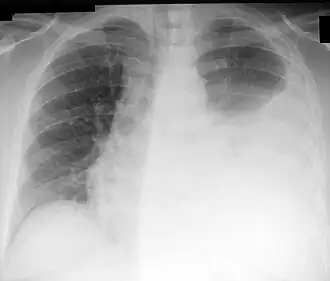

La ponction pleurale est généralement utile une fois le diagnostic d’épanchement pleural confirmé par la radiographie de thorax. De plus, l’analyse du liquide pleurale permet d’éliminer les étiologies nécessitant un drainage pleural urgent (par exemple lors d’une pleurésie purulente ou d’un hémothorax). C’est un acte peu invasif et les résultats de l’analyse du liquide pleural permettent une orientation étiologique dans 75 % des cas, ce qui implique un rapport bénéfices-risques assez élevé.

Une radiographie pulmonaire est réalisée avant l'opération; permettant de visualiser l'importance de l'épanchement et son côté. Comme avant la plupart des opérations, il est important de renseigner le patient sur les étapes de son déroulement. Une ponction pleurale se réalise sur un patient en position assise et en l'abordant par la partie postérieure de son thorax. Le niveau de la ponction est repéré par percussion de la paroi (matité). Après désinfection, l'anesthésie est effectuée. L'aiguille, munie d'une seringue, est insérée au niveau du site de la ponction, juste au-dessus de la côte inférieure, afin d'éviter nerfs et vaisseaux sanguins du paquet vasculo-nerveux qui se situe en dessous de la côte supérieure. Lorsque l'aiguille arrive au niveau de la plèvre (reflux de liquide) on effectue les prélèvements ou le drainage. L'aiguille est ensuite retirée d'un coup et un pansement est mis en place. Une échographie pleurale est parfois réalisée en même temps, ou peu avant pour guider plus facilement la ponction pleurale, permettant d'avoir un taux de complication moindre[2],[3]. Cette technique est particulièrement intéressante en cas d'un épanchement de petite taille ou cloisonné[4].

Après l'opération, il est important de surveiller les constantes du patient. Une radio pulmonaire de contrôle est réalisée pour contrôler le niveau de l'épanchement et l'absence de pneumothorax, mais son utilité dans les cas simples reste discutée[5].